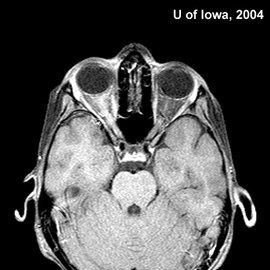

腦脊液檢查發現白細胞及蛋白質多輕度或中度增加,但也可正常。寡克隆區帶、IgG鞘內合成率等免疫指標多為陽性。影像學檢查(CT、磁共振)可顯示病灶,特別是大腦半球的病變。其典型所見是位於腦室周圍及皮質下白質的多發病灶。

診斷要點為多發性病灶及緩解、復發的病程。電生理(誘發電位)和影像學檢查可發現臨床下病灶,有助於診斷。腦脊液免疫指標的異常可支持臨床診斷。